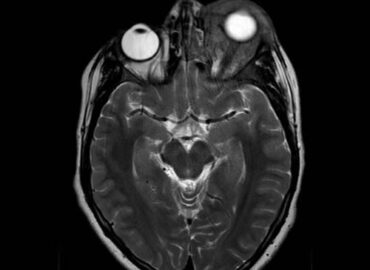

Paciente de 14 años de edad, que consulta por edema palpebral izquierdo de 15 dias de evolucion.

Edema palpebral de ojo izquierdo